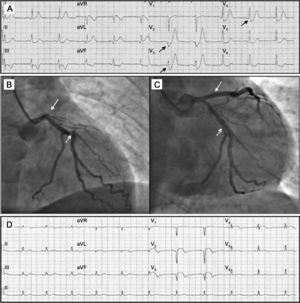

El primer caso es un varón de 61 años, sin antecedentes cardiológicos de interés, atendido en su domicilio por los servicios de emergencias por dolor torácico agudo. En el primer ECG realizado (figura 1A), aproximadamente tras 30min de dolor, se observa un marcado descenso del segmento ST, de hasta 3mm, a expensas del punto J, con onda Q y ondas T picudas en derivaciones precordiales V2-V5, ascenso del segmento ST de 0,5mm en aVL y aVR y descenso del ST de 1mm en derivaciones de la cara inferior. El paciente fue remitido al laboratorio de hemodinámica, donde se observó la oclusión total de la arteria descendente anterior proximal (figura 1B), sin relleno colateral. Se trató la lesión con angioplastia e implante de stent farmacoactivo. En el mismo procedimiento, se trató exitosamente dos lesiones del 70% en la arteria circunfleja y en la arteria coronaria derecha mediante angioplastia e implante de stents (figura 1C). En el ECG realizado tras el procedimiento (figura 1D), se observan alteraciones eléctricas características del infarto anterior en evolución, con complejos QS V1-V2, rS en V3, ascenso persistente del ST y negativización de la onda T.

A: electrocardiograma tras 30min del inicio del dolor; se observan los «complejos de De Winter» en derivaciones V2-V4. B: oclusión de la descendente anterior proximal (flechas) y la estenosis significativa de la circunfleja (flechas punteadas). C: coronariografía tras la angioplastia; se observa la restauración del flujo en la arteria descendente anterior (flecha) y la lesión de la circunfleja, ya tratada (flecha punteada). D: electrocardiograma tras el procedimiento; imagen de infarto anterior evolucionado, con Q V1-V2 y ascenso persistente del ST V2-V5, I y aVL.